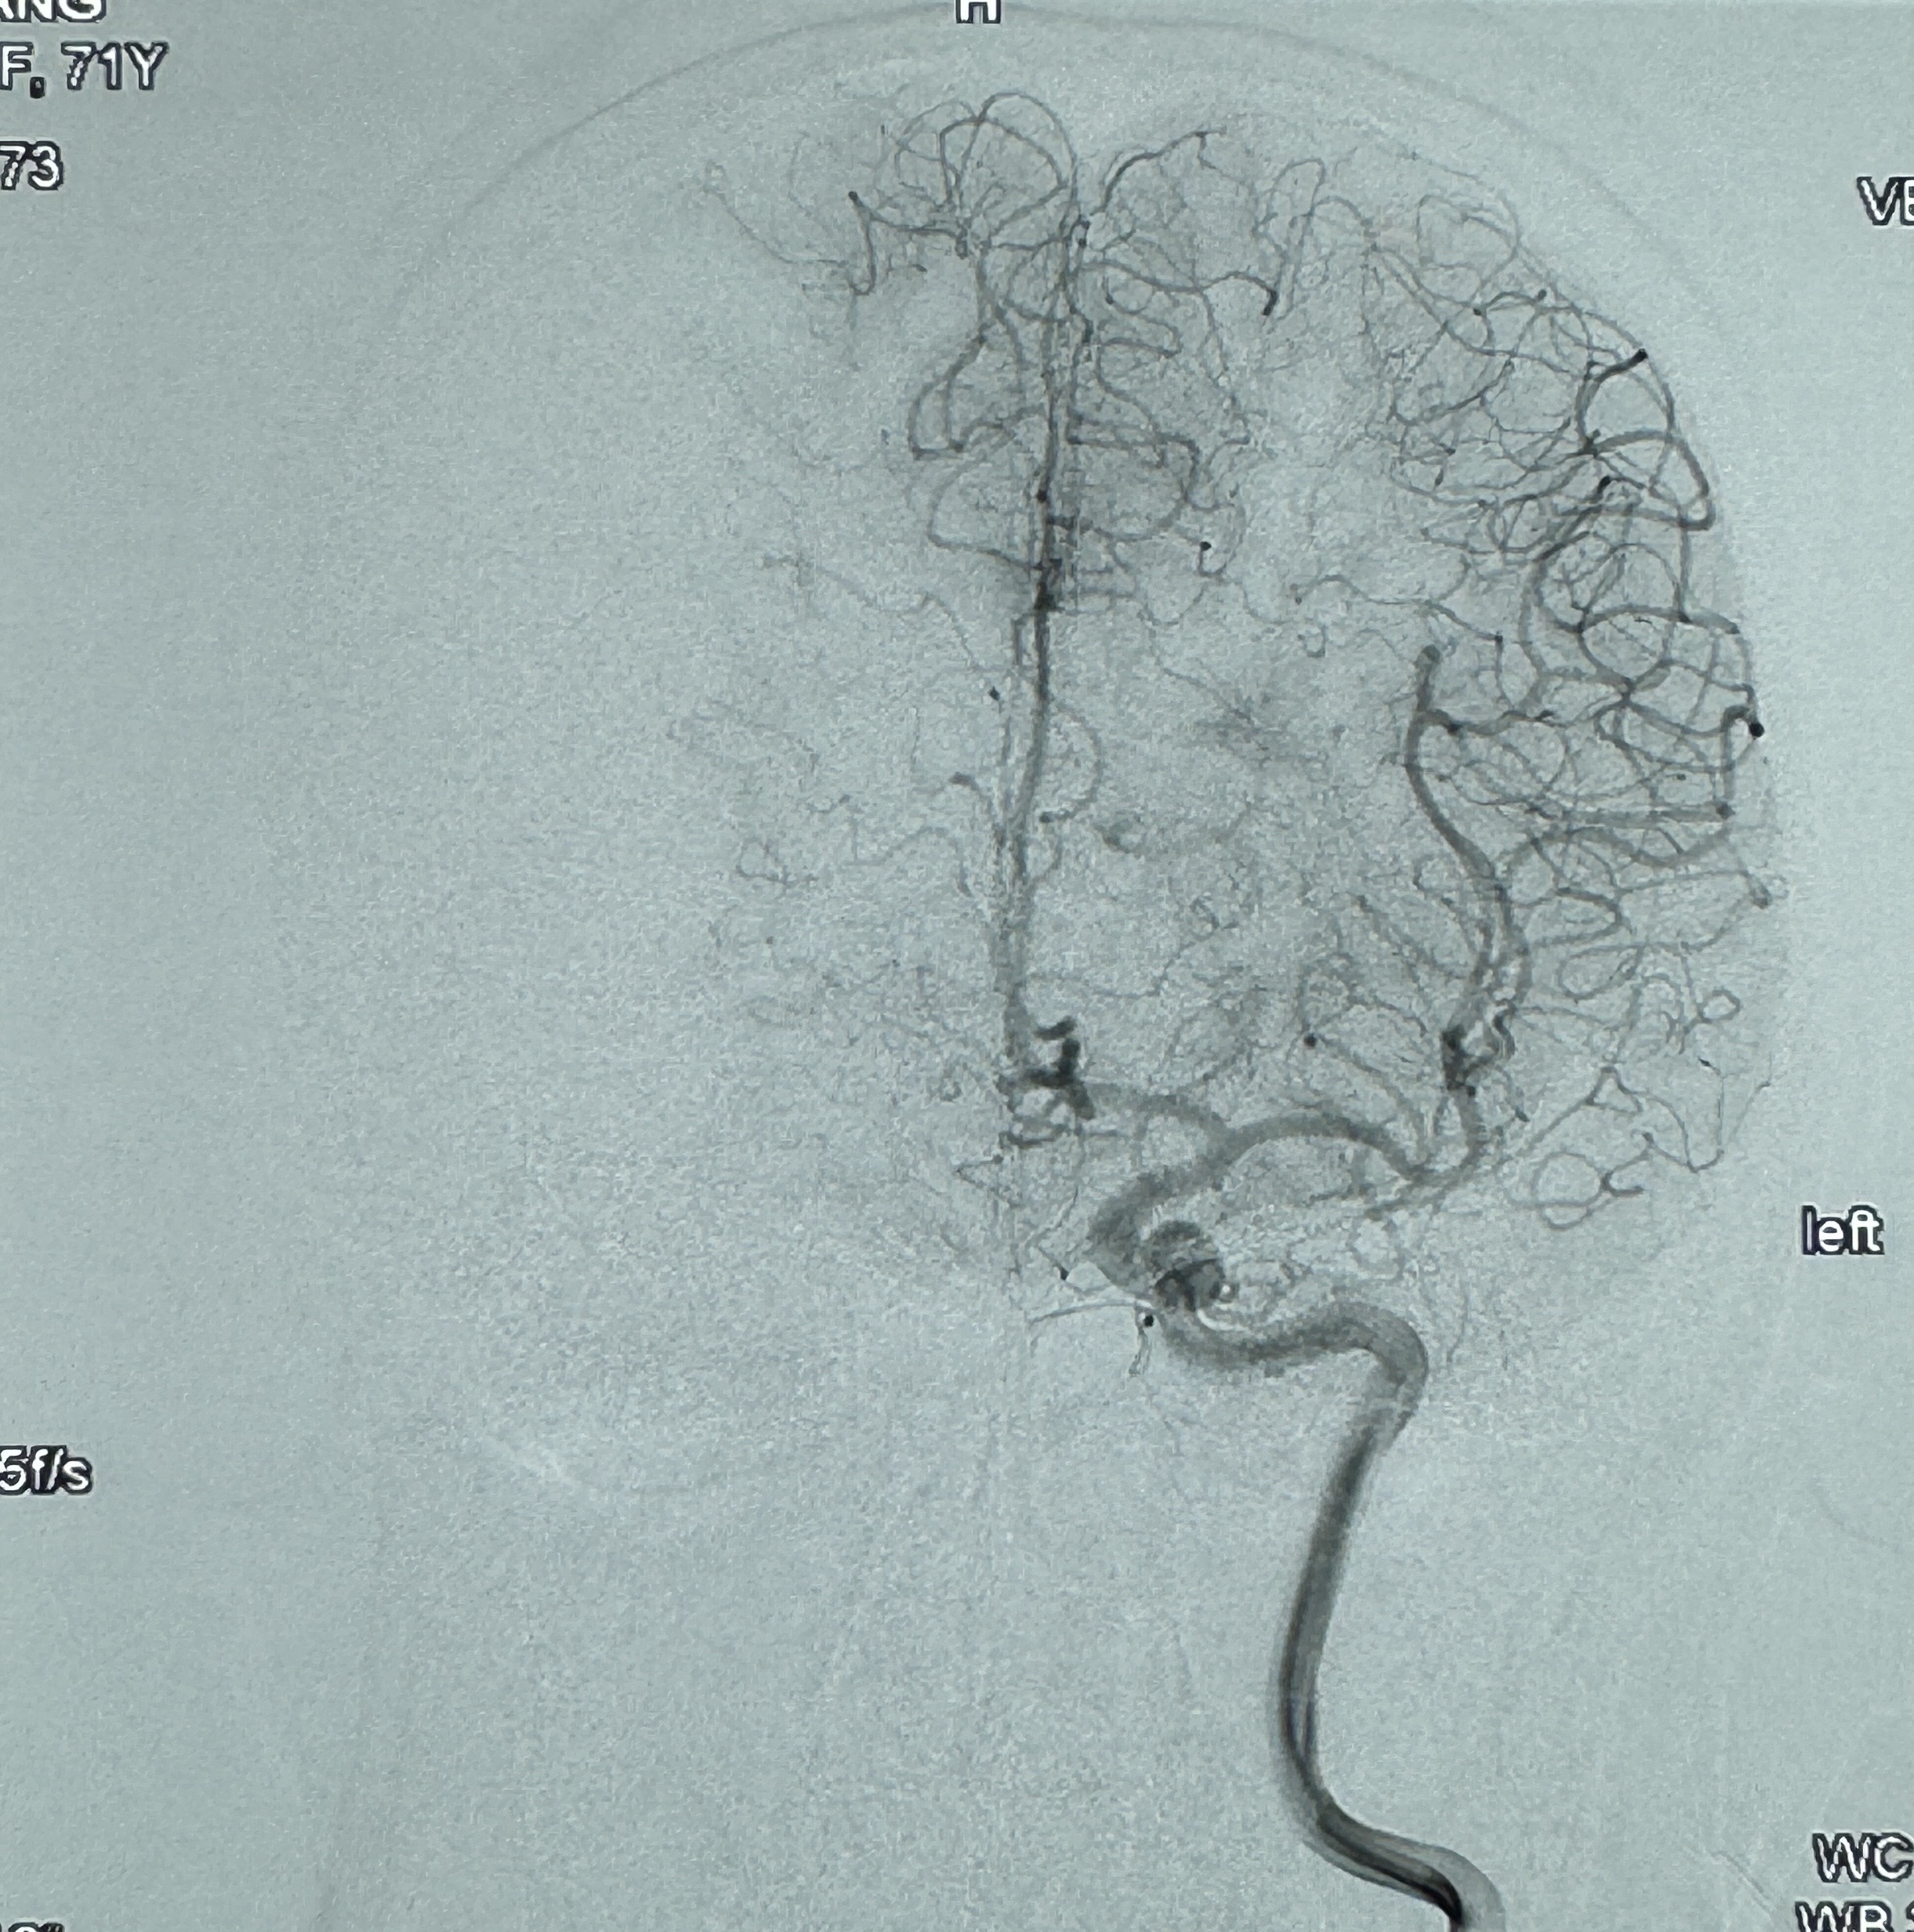

2023-12-27术后第十天复查DSA

支架贴壁佳,但可见射流,咋办?

2024-01-08全麻下再行植入密网支架一枚

Tubridge 4.5-35mm

支架植入顺利,贴壁佳,支架内血流通畅,动脉瘤内血液滞留明显